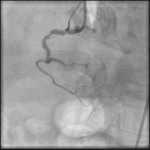

A 72-year-old man presented with acute onset of chest pain and shortness of breath. Found to have ST elevation in inferior leads and then cardiac catheterization lab was activated for…